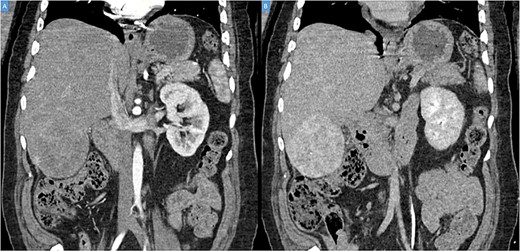

A 49-year-old male presented with a large right hepatic lobe mass on abdominal computed tomography (CT) scan ordered for non-specific abdominal pain. He had a past medical history of type 2 diabetes mellitus, glaucoma and deafness due to mumps. The physical examination was normal, with a body mass index of 22 kg/m2 and no previous abdominal surgeries. CT scan (Fig. 1A and B) and magnetic resonance imaging (MRI; Fig. 2A and B) revealed a 10.7 × 7.6 × 8.9-cm mass involving the liver’s segments V–VI with heterogeneous enhancement and areas of calcification.

(A, B) Coronal computed tomography of the abdomen showing a large tumor on liver’s segments V–VI with heterogenous contrast enhancement.